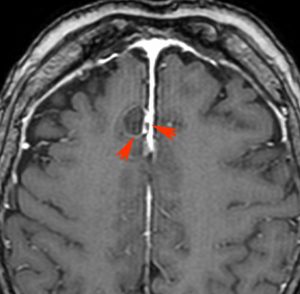

第3脳室内のadamantinomatous craniopharyngiomaです。これを両側前頭開頭,経脳梁法 transcallosall approachで摘出しました。下垂体と下垂体柄を温存するためです。

初回手術から6年後,原発部位に腫瘍はありません。しかし,前頭部大脳鎌(赤矢印)に腫瘍が発生しました。これは手術経路(緑の線)に沿った位置にあるので,drop metastasisだとわかりました。病理は初回と同じものです。このdrop metastasisは意外に多いものです。頭蓋咽頭腫は,極小の腫瘍片でも脳表や脳槽にこぼれ落ちれば,そこで着床して,数年後に再発となって現れるということを示しています。ですから,手術の時に断片を残したり落としたりしてはなりません。